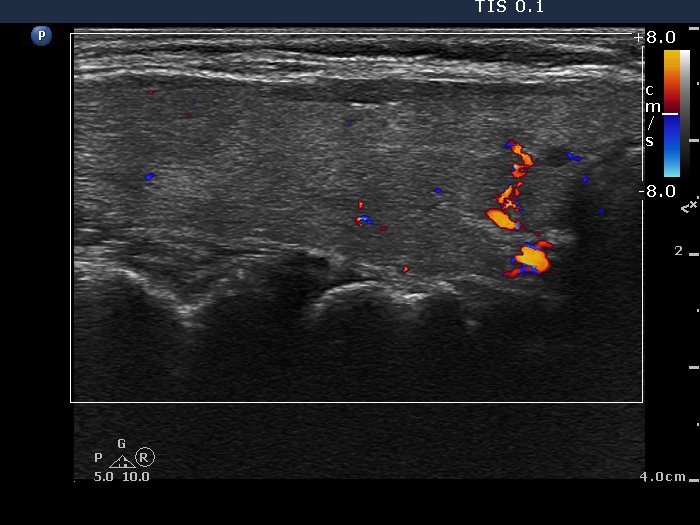

Intranodular hyperechogenic figures - case 1789 (ultrasonographic picture 3)

Right lobe, longitudinal view, color Doppler mode. There is a large vessel in the lower part of the lobe.